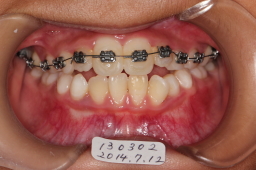

2014年07月12日

ワイヤーの拡大で上顎切歯の空間がある程度出来ました。